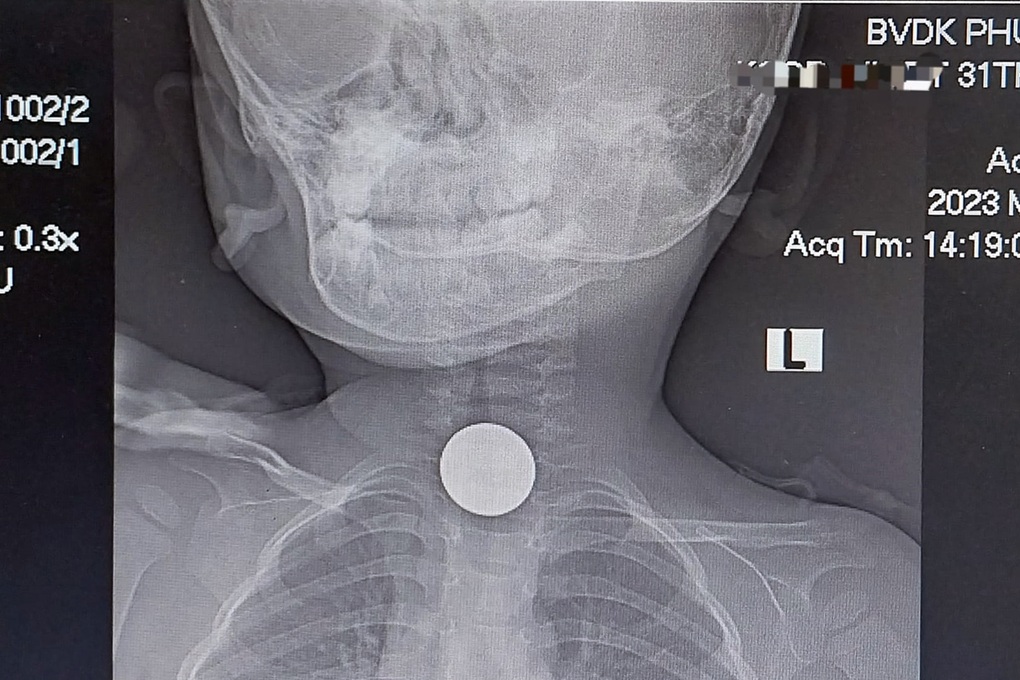

Hình ảnh chụp X quang phát hiện đồng xu mắc ở cổ của N. (Ảnh: Bệnh viện Phú Yên).

Qua chụp X quang, bác sĩ phát hiện dị vật ở thực quản đoạn cổ của bệnh nhi. Ngay lập tức, cháu bé được gây mê, nội soi lấy dị vật là 1 đồng xu ra ngay.